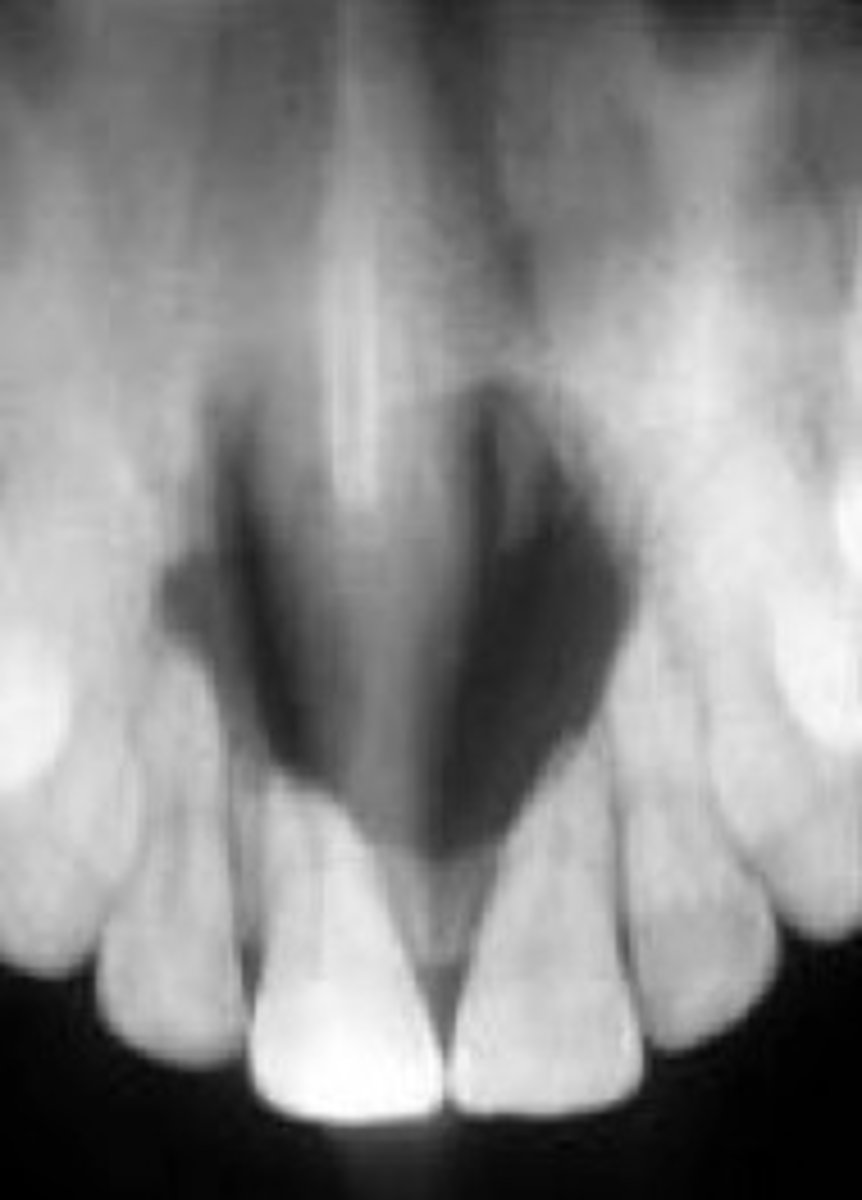

What are radiographic features of nasopalatine duct cysts?

well-defined radiolucency btwn maxillary central incisors

• "heart-shaped" **KNOW FOR EXAM